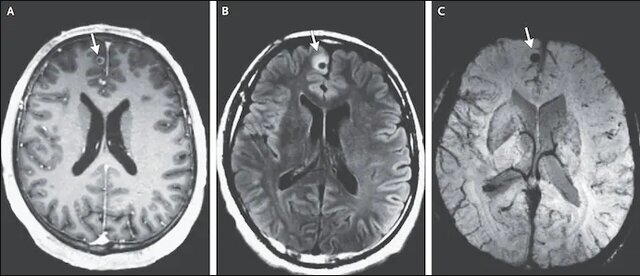

پس از انجام آزمایشات مختلف، پزشکان سه ضایعه مغزی را کشف و بیماری این مرد را سیستیسرکوزیس عصبی اعلام کردند. پزشکان گفتند که این بیماری نوعی عفونت بافتی است که کرم نواری عامل به وجود آمدن آن است. کیستهای لارو کرم نوازی حدود دو دهه قبل به مغز این مرد وارد شده و در بخشهایی از مغز قرار داشتند.

کرم نواری در این مرد ماساچوستی پس از دو دهه باعث ایجاد عفونت شده بود. پزشکان توانستند تشنج این مرد را با دارو کنترل و او را تحت درمان با داروی ضدانگل و ضدالتهاب قرار دادند. او پس از پنج روز و بدون هیچ علائمی از بیمارستان مرخص شد. این مرد به مدت سه سال مورد آزمایش قرار گرفت و پزشکان دریافتند که تورم اطراف بزرگترین ضایعه مغز این مرد کمتر شده و با مصرف دارو دیگر دچار تشنج نشده است.